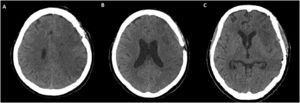

Vasospasm was diagnosed in patients by either CTA, DSA, or TCD ultrasonography, with 37.8%, in this cohort. DCI occurred in 30 patients (36.6%), and the mean day of presentation was 6.89 (±4.59). There was a good correlation between vasospasm and DCI, as this coexisting phenomenon occurred in 16 of 30 patients (53.3%). Twenty-five patients (30.5%) had hydrocephalus, 20 patients (24.4%) had an intracerebral hemorrhage, and 14 patients (17.1%) had global cerebral edema on admission CT. In TCD, the highest peak systolic blood flow velocity and mean blood flow velocity were 296 and 199.92 cm/sg, respectively, while the lowest values reported in the sample were 25.48 and 14.76 cm/sg for the middle cerebral artery in 62 patients. Twenty patients had an inadequate window for the middle cerebral artery.

Clinical characteristics and ultrasound parameters of patients with and without DCI are compared in Table 1. Smoking history, high values of systolic blood pressure, GCS, global cerebral edema, intracerebral hemorrhage, hydrocephalus, angiographic vasospasm, type of intervention, diameter>10 mm of the aneurysm, the presence of anatomic variants, peak systolic velocity, and mean flow velocity were all associated with DCI (Table 1). In particular, patients with DCI had higher values peak systolic flow (median, 89.95 [IQR 61.75–138.45] vs median, 62.74 [IQR 41.59–90.79]), and mean flow velocity (median, 52.46 [IQR 32.43–79.37] vs median, 36.35 [IQR 22.74–60.68]) (Fig. 1).

Box-plot of peak systolic velocity and mean flow velocity corresponding to delayed cerebral ischemia. In the box-plot, the central rectangle spans the first quartile to the third quartile (interquartile range). A bold segment inside the rectangle shows the median and “whiskers” above and below the box showing the minimum and maximum; outside box-plot points are outliers.

The most recent and updated meta-analysis of TCD for the diagnosis of vasospasm in the middle cerebral artery shows that both conventional and color Doppler are likely to detect vasospasm, but neither is useful to exclude one.42 In the case of DCI, TCD was also proved to have a high sensitivity (90%) (95% confidence interval [CI] 77%–96%), and predictive-negative value 92% (95% CI 83%–96%).41 However, TCD is not a mandated standard of care in aSAH due to the paucity of evidence on clinically relevant outcomes, and there is a need for high-quality for randomized trials.41 In our study, none of the parameters evaluated by TCD were statistically significant in the logistic regression; however, the mean values for systolic peak flow and mean flow velocity in the group with DCI compared to those who did not develop it was higher as depicted in the boxplots (Fig. 1).